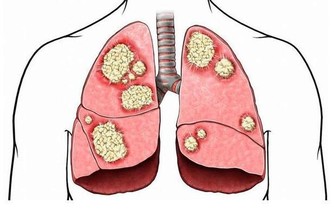

過敏性鼻炎不僅表現為一些打噴嚏、流鼻涕、鼻塞的鼻部症狀,

如果不積極做好防控,還可能會引起其他相關疾病,

如黑眼圈、眼睛瘙癢、鼻子瘙癢、蕁麻疹、濕疹,長期不治療,還可能會導致過敏性哮喘

醫學資料顯示,約10%左右的過敏性鼻炎患兒,有可能發展為哮喘患者;

而患哮喘的孩子中,同時患有鼻炎是個很常見的問題。